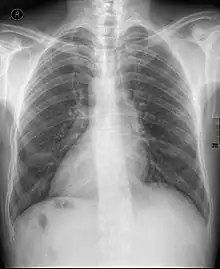

| Chest X ray of a person with dextrocardia situs inversus showing the cardiac apex pointing towards right | |

Dextrocardia situs inversus refers to the heart being a mirror image situated on the right side. For all visceral organs to be mirrored, the correct term is dextrocardia situs inversus totalis.[4][5]